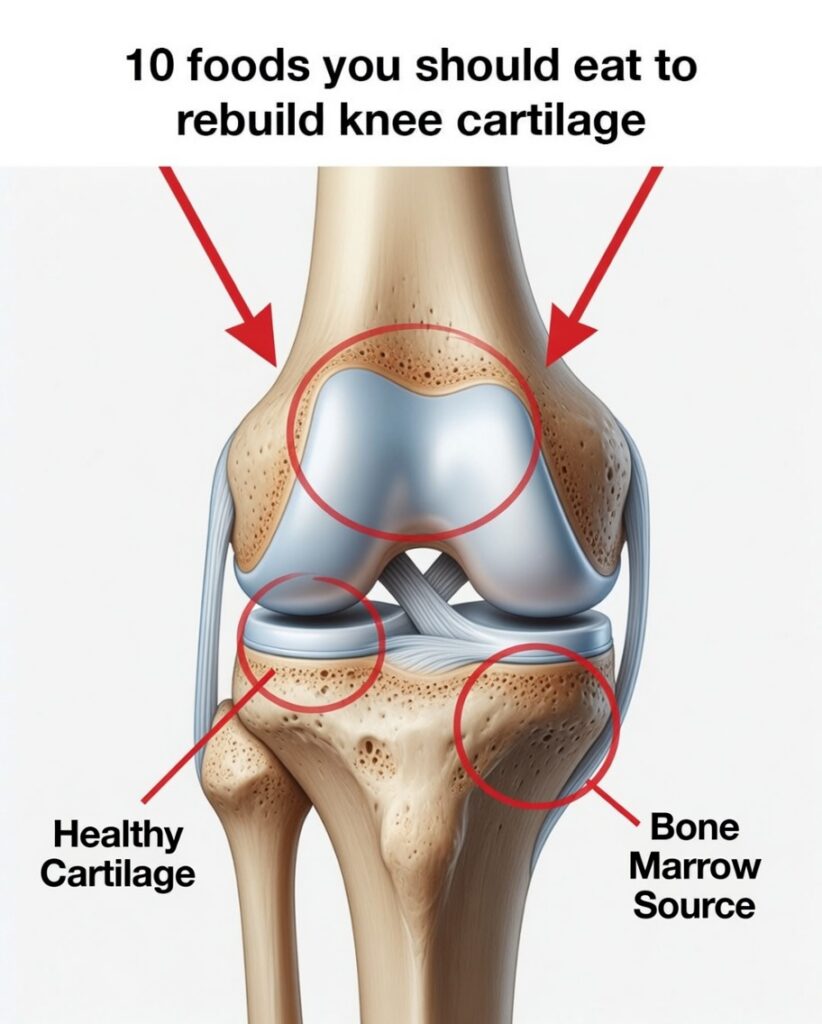

Grandma’s Natural Method for Cartilage Regeneration and Joint Support

Cartilage is essential for smooth, flexible movement because it cushions your joints and helps them glide without friction. Over the years, daily wear, aging, or injuries can weaken cartilage, leading to stiffness, discomfort, and reduced mobility. While medical treatments can help, many people also look to traditional, natural joint remedies passed down through generations.

1. Bone Broth for Collagen and Minerals

Bone broth was considered the go-to tonic for joints. It naturally contains collagen, amino acids, and minerals that support connective tissue and may help improve joint comfort and flexibility over time.

2. Gelatin-Rich Foods to Support Cartilage Structure

Because gelatin is derived from collagen, it has long been used in traditional diets to help with joint lubrication and cartilage support.